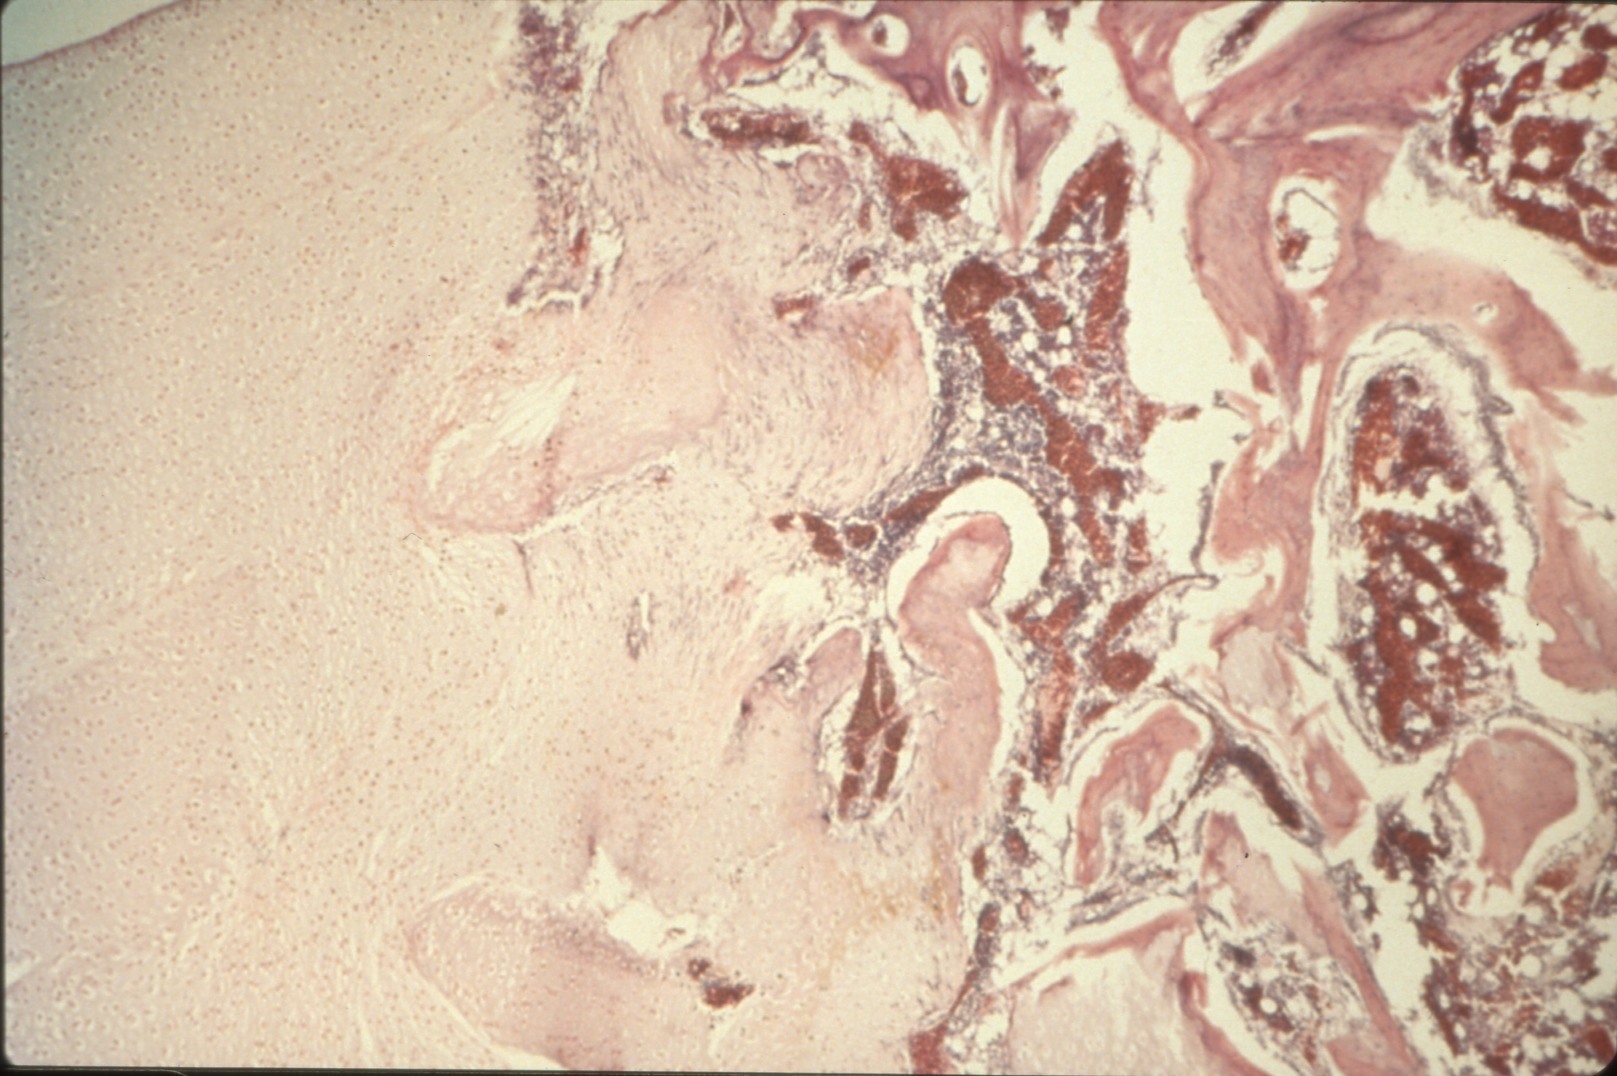

Tibial dyschondroplasia in domestic poultry (slide study set no. 6) Item Info

Tibial dyschondroplasia in domestic poultry (slide study set no. 6)

Avian medicine Poultry--Diseases Tibia

Slide Study Set #6, Tibial Dyschondroplasia, 2 sets (includes 34 color slides), 1975